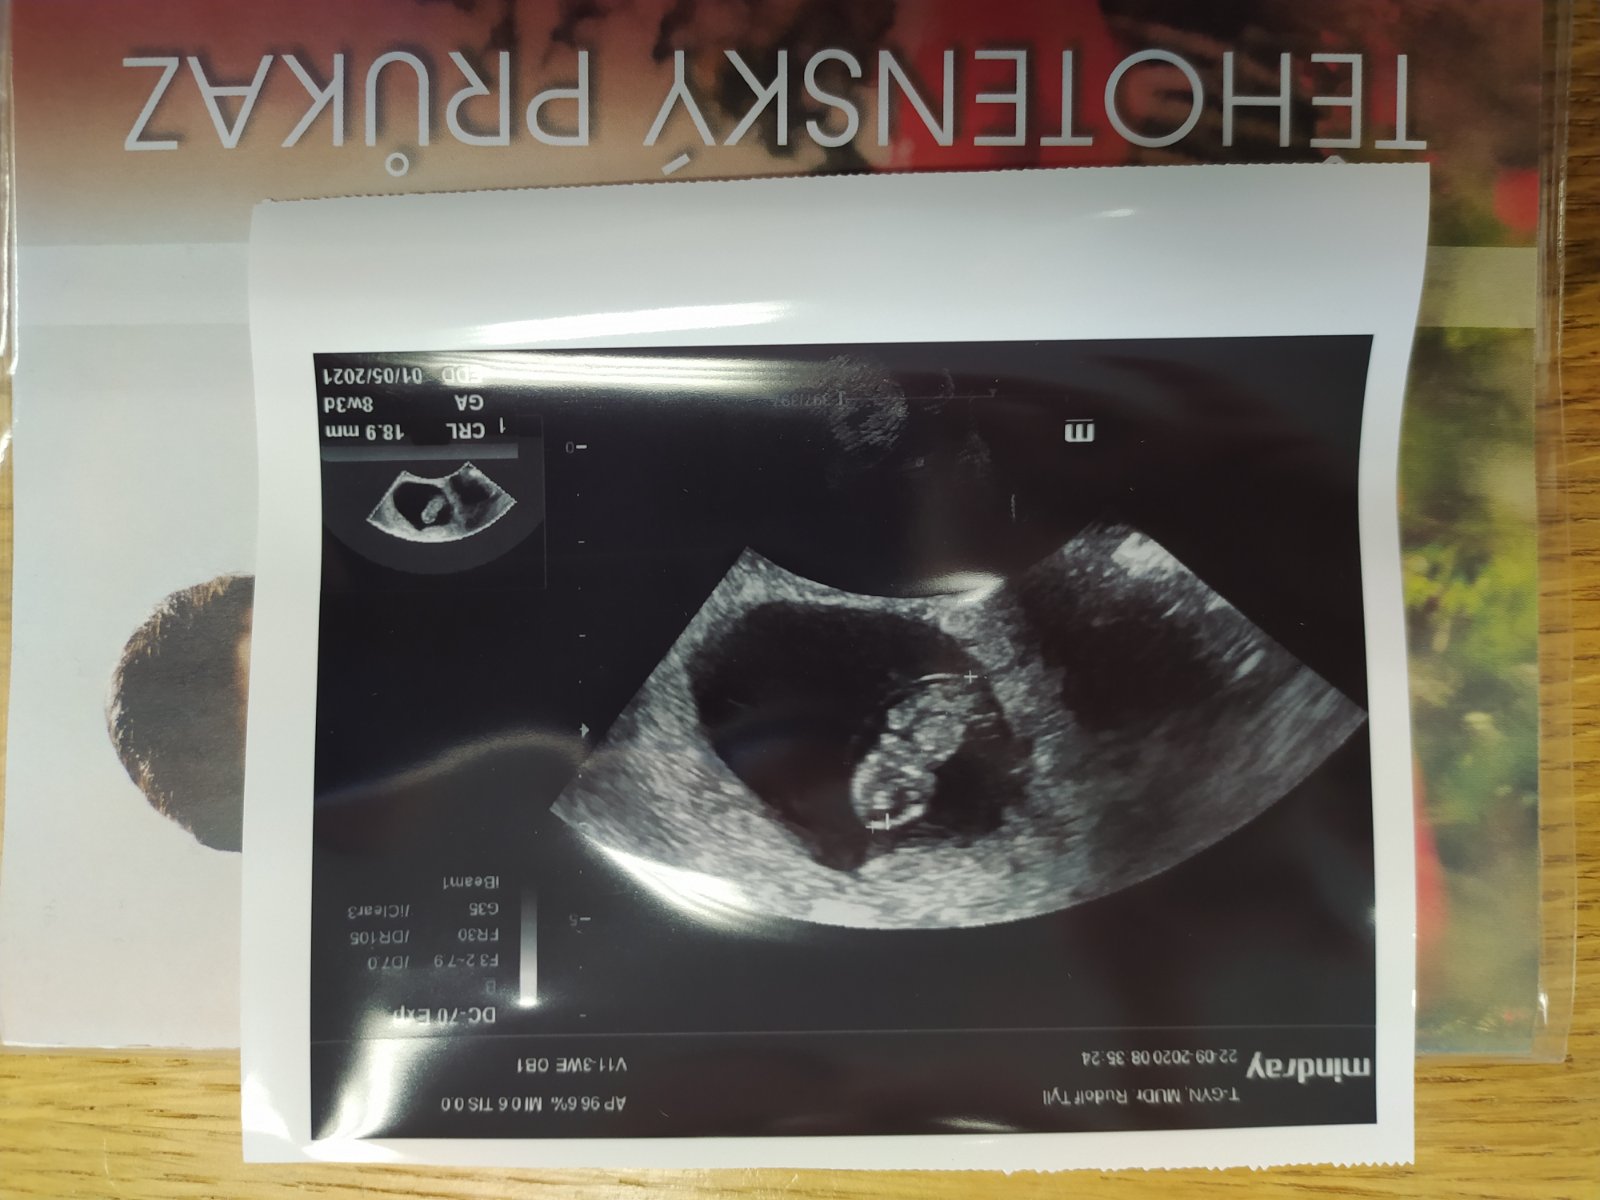

Tak jsem po kontrole, dnes 8+3 a krásně nám bije srdíčko 🥰 nezažila jsem větší pocit štěstí

Holky ve středu jsem byla na ultrazvuku.Vse ok,byla jsem 8+5.Ale jak teď začíná 10. Týden přestávám být unavená a i nevolnosti se vytraci...jak to máte Vy?